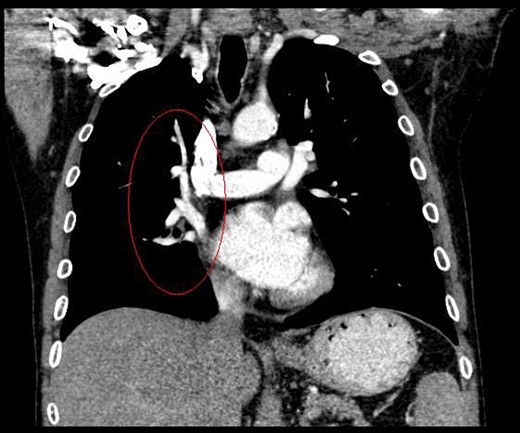

During discussions at the multidisciplinary team meeting, the computed tomography scans of his thorax were reviewed by our radiology colleagues and an anomalous right upper lobe vein was identified.

The patient underwent a right postero-lateral thoracotomy. The right upper lobe pulmonary artery and vein were identified and divided with vascular Endo GIA™ staples. Lymphadenectomy was performed in the draining lymph nodes and we proceeded to isolate the upper lobe bronchus. Prior knowledge of an anomalous venous drainage of the upper lobe made us adopt a cautious approach during dissection posterior to the right upper lobe bronchus and a vascular structure was identified that could be traced in the left atrium; thus, it was found to be an anomalous upper lobe pulmonary vein. The anomalous vein was divided with vascular Endo GIA™ staples. The bronchus was divided with a TA™ stapler.

Kim et al. [2] first reported the contrast-enhanced computed tomography findings of aberrant pulmonary veins, which were observed as a focal nodularity attached to the posterior wall of the bronchus intermedius. Pulmonary vein variations are usually seen in the common pulmonary vein and the middle lobe vein draining into the inferior pulmonary vein or the left atrium [3]. There are only a few CT studies of the upper lobe vein. The frequency is reported between 1.7 and 5.7% [3].

Kim et al. [2] eluded that in 5% of normal subjects, the right superior segmental pulmonary veins had an aberrant course also either to the inferior pulmonary vein or directly to the left atrium. Asai et al. [4] noted that in right lung resection surgeries, there was a 5.7% occurrence of abnormal right upper lobe venous drainage.